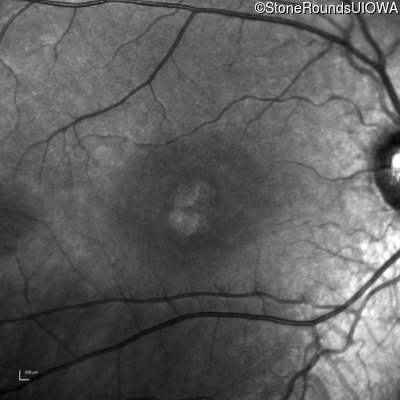

Infrared Fundus Photograph - Right - 20/200

Exemplar